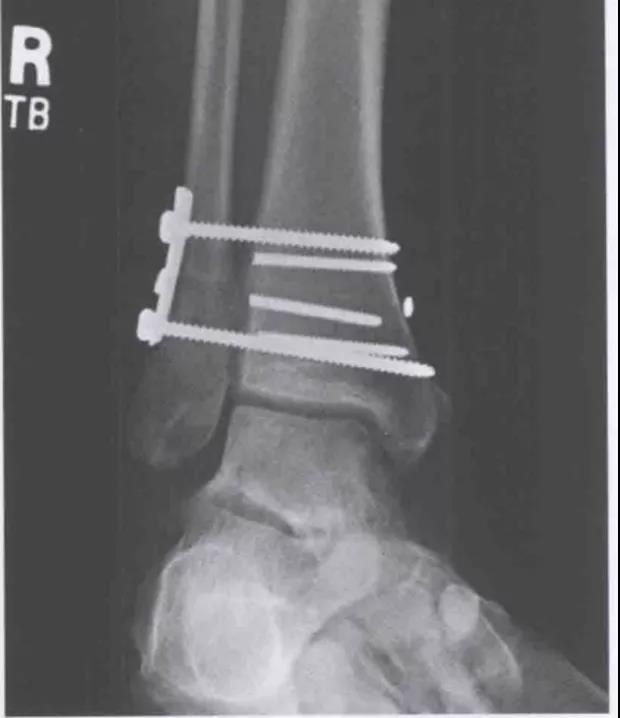

固定方法1、螺钉固定:在下胫腓联合上方1~3cm处,用1~2枚3.5mm皮质骨螺钉平行关节面向前倾斜30贯穿2层腓骨及1层胫骨皮质,在踝关节轻微背屈位固定,不做加压。2、胫腓钩(Link)3、endobutton,可吸收钉等

下胫腓固定一枚还是两枚螺钉?

双重固定

术前DR

术中: